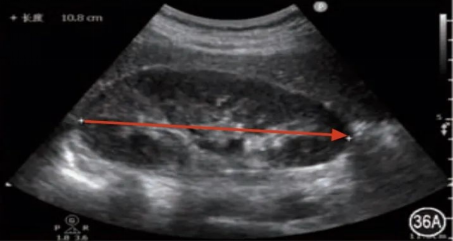

首先,我们来认识一下传统的“黑白超”。它的学名是“二维灰阶超声”,是超声成像中最基础的形式。黑白超通过向人体发射超声波,并接收从器官或组织反射回来的信号,再根据信号强弱,以不同深浅的黑白色调构成图像。这种图像虽然颜色单一,但能非常清晰地显示出脏器的轮廓、大小、形态以及内部结构,是医生评估器官是否健康的重要依据。

在用途上,黑白超主要用于观察器官的形态与结构,例如检查肝脏是否均匀、胆囊有无结石、胎儿发育是否正常等。而彩超中的彩色功能,则在评估血流方面发挥着重要作用——比如判断甲状腺结节的血供特征、诊断心脏瓣膜疾病、评估肿瘤的血液供应情况等,为医生提供更丰富的诊断依据。